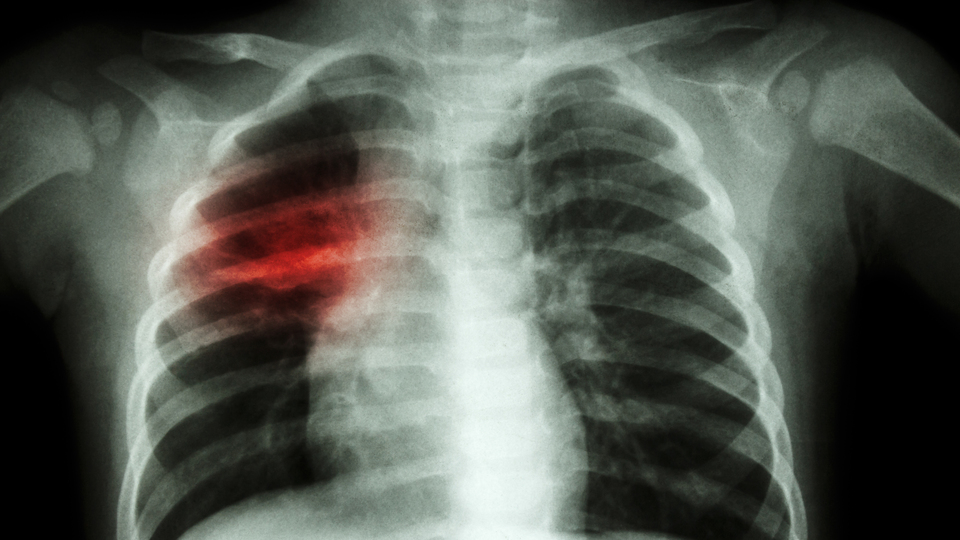

Dr. Stephan Gibson ise, ProMed ağında paylaştığı mesajda, bakteri kaynaklı bir solunum yolu enfeksiyonu olan "mikoplazma zatürresinin" öksürüğün hastalığın temel belirtisi olduğu fakat çocuklarda öksürük yerine üst solunum yolu semptomlarının, mide bulantısı ve kusmanın görülebileceği değerlendirmesinde bulunmuştu. Öte yandan Gibson, mikoplazma zatürresinde solunum yollarında "yanma tarzı infiltrasyonların" görüleceği, bu vakalarda akciğer röntgenlerinde görülen iltihaplanma bulgusunun anomali oluşturduğuna dikkati çekmişti.

Çocuk Sağlığı ve Hastalıkları Uzmanı Dr. Şirin Seçkin, "Çin'de günde 3,500 çocuk yüksek ateş ve zatürre nedeniyle hastaneye yatırılıyor. Çin'deki çocuklar zatürre nedeniyle hastaneye yatıyor. İstatistikler vakaların bu aylarda geçen yıla oranla üç kat arttığını gösteriyor. Çin’de beyaz akciğer zatürresi diye geçiyor. Bu vakalarda hastaların röntgenlerinde tüm akciğer beyaz gözüküyor" dedi.